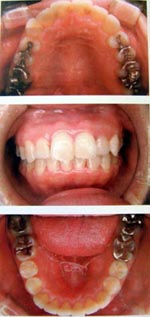

子供の場合・1日10時間装着

空間を広げ呼吸を楽にします。